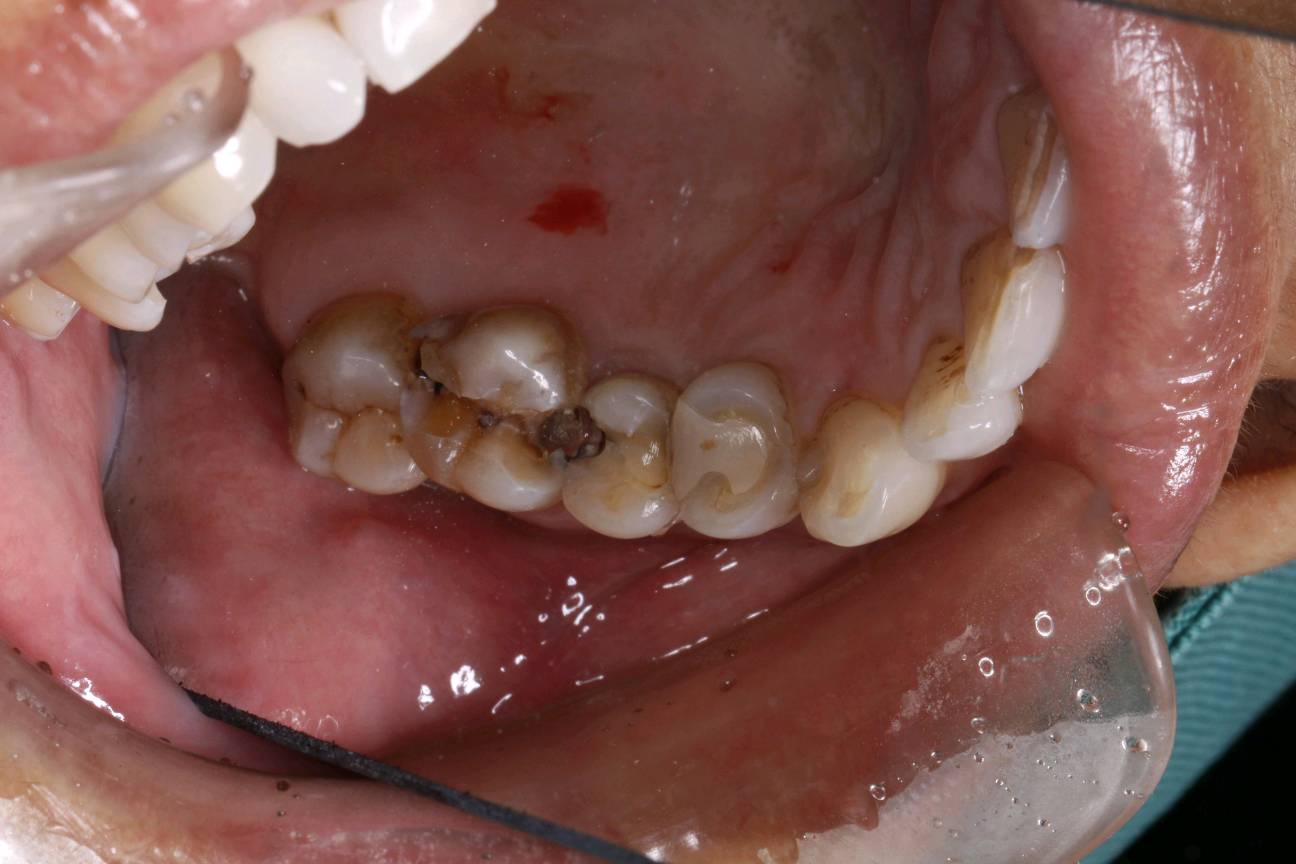

患者女,三十岁,15,17邻颌面龋坏,,16继发性龋坏。探(+-),叩(-),冷测试正常,余无不适。很多人牙体缺损面积较大,补牙后很会出现脱落的现象,还有的让选择简单的修复模式补牙,但大量的临床研究显示,牙科树脂充填材料会产生聚合收缩(树脂材料老化),形成微渗漏,引起继发龋(顺着充填材料周围,在牙齿上出现新的腐坏、变黑)。像这种面积比较大的龋齿单纯补牙的话,不耐用。这时候就可以选择嵌体修复。嵌体牙体预备量少,能够保持牙齿外形的完整,减少对牙髓的刺激。还有就是嵌体更耐磨使用寿命较长,从而减轻了患者频繁补牙的痛苦。通过 CEREC 扫描更加精准有效的提高了我们工作效率,当天即可戴牙,正常使用。